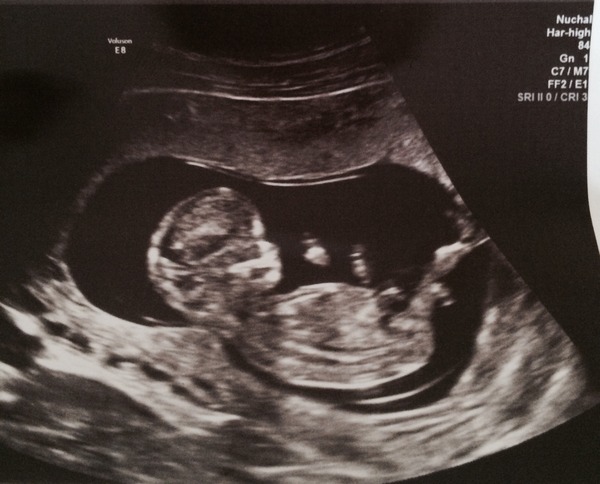

Here's my 12 week (12+4) scan, had mixed opinions on gender so far but husband is a family of boys boys boys, so expecting boy!

spydie I think girl! Smile

spydie lovely pic - and I think girl too. Are you planning on finding out? I was convinced I'd be having a boy too as only boys on dh's side and I have two boys already, but nope it's a girl - was a big surprise.

Thanks Kep1979, we actually got loads of pics, about 10! Yes we are going to find out. I (awfully!) would prefer a girl, I know I won't mind once it's here but we both want to find out!